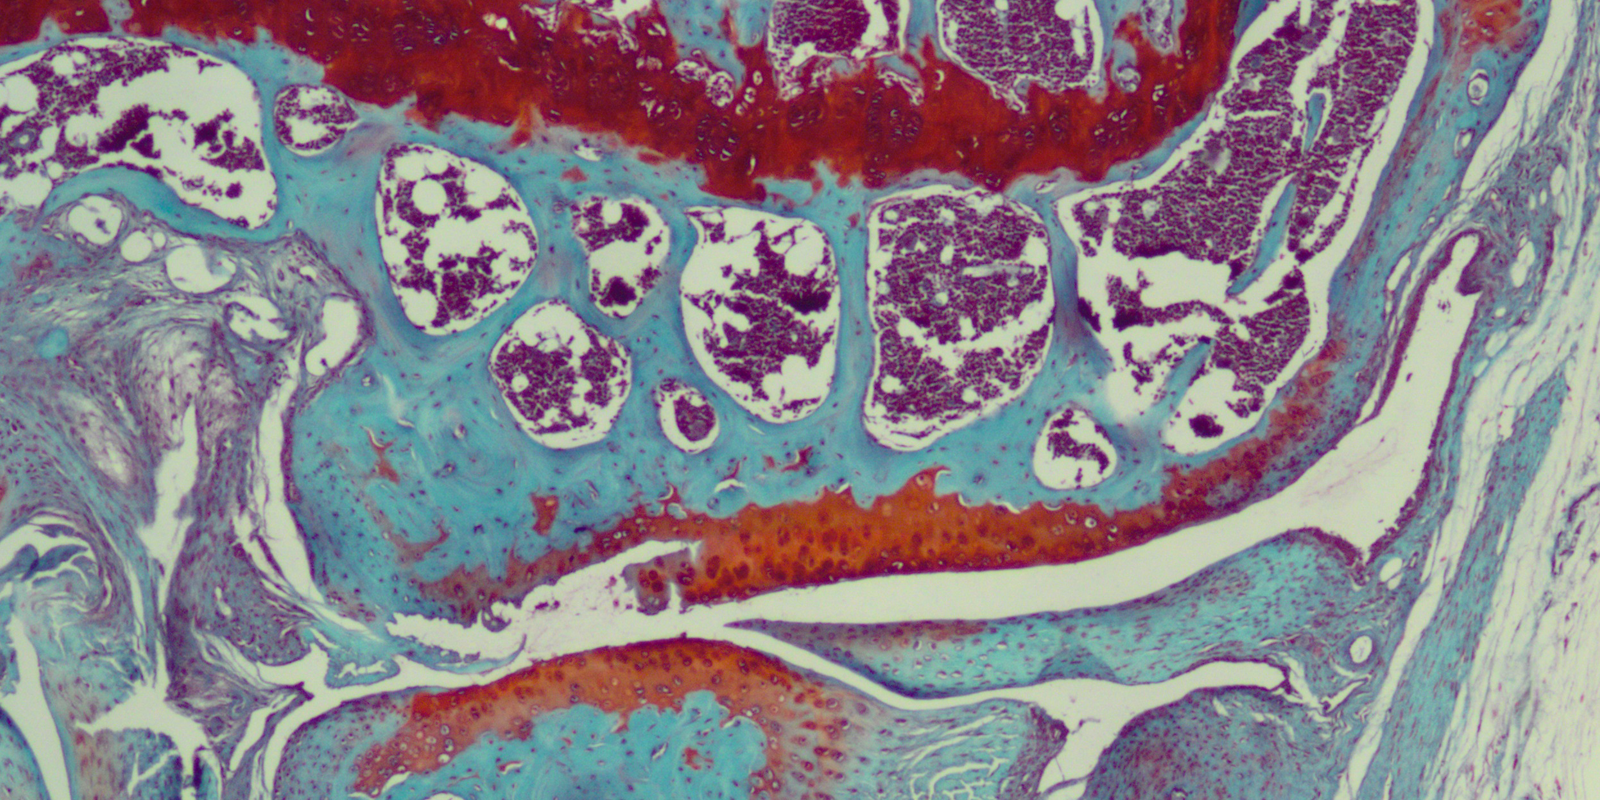

Partial thickness defects or Mild Cartilage Injuries – macroscopically or examined by the unaided eye, they can be identified by softness and afterward by fibrillation of the cartilage, i.e., by the formation of some fibrous scar tissues. These scarred areas are thick with no access to bone marrow stem cells, which leads to a low ability to spontaneous or natural repair. Those defects evolve with time, being associated with swelling and mechanical symptoms caused by detachment of cartilage flaps that happens when cartilage separates from the bone and moves like a door with a hinge at one end